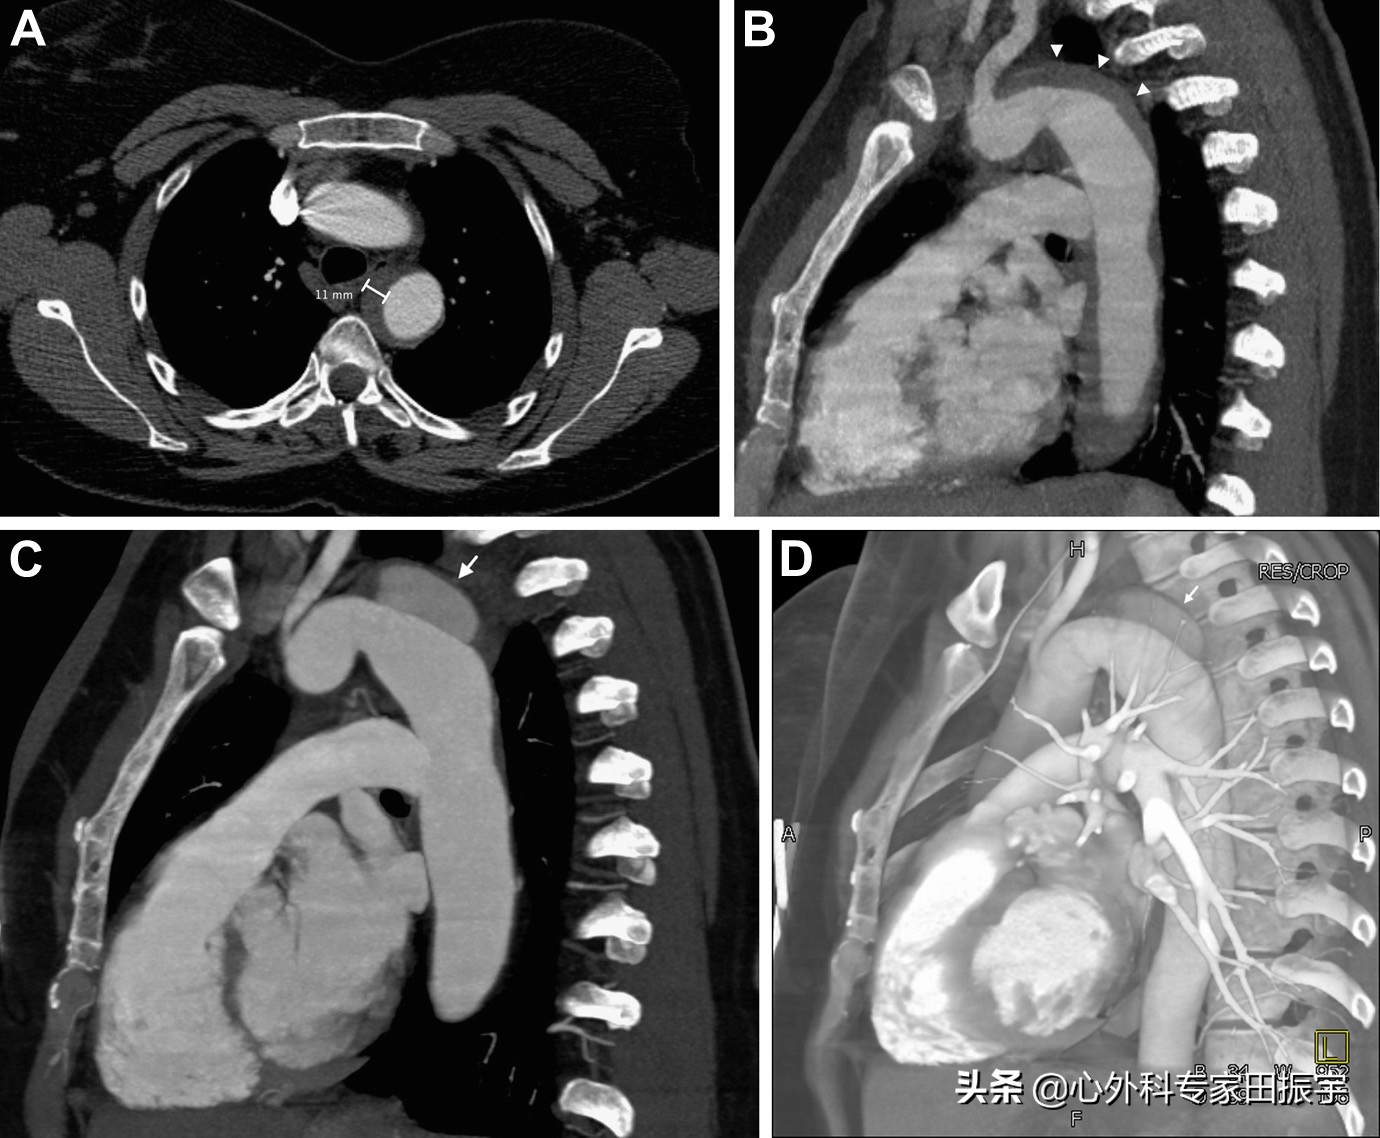

来自Stanford A型IMH的药物治疗患者的数据表明,CT测量上壁间血肿厚度的增加与夹层、主动脉扩张、手术干预、破裂和死亡有关。血肿厚度 大于11 到 16 mm 已被证明可以识别这些并发症风险增加的患者,IMH 厚度预测不良事件与最大主动脉直径无关(图 4)。相反,壁间血肿厚度为 小于10 至 11 mm,可预测 30 天内出现并发症的风险较低,IMH 吸收的可能性更大(图 5)。

主动脉壁间血肿

图4 一名43岁妇女出现急性背痛和高血压危象。增强CT的轴向(A)和矢状多平面重建(B)CT 图像显示 B 型壁间血肿,血肿厚度为 11 mm(箭头)。3 个月后随访增强CT多平面重建图像(C)和三维体积重建图像(D)显示主主动脉弓远心端发展成假性动脉瘤(箭头)。